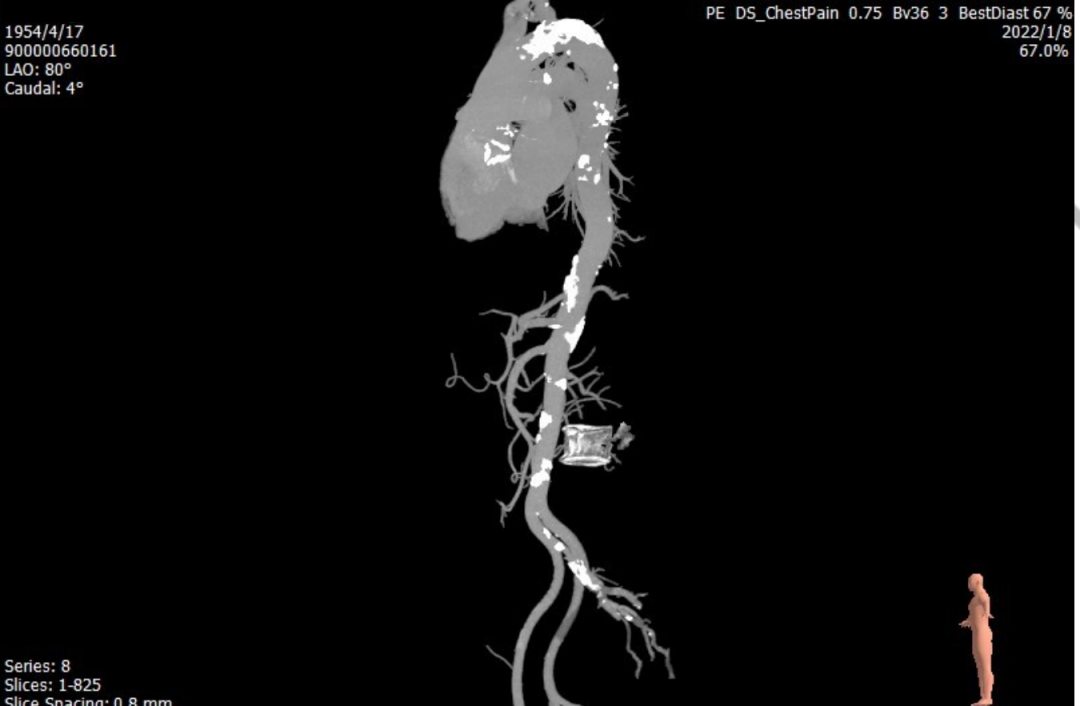

主动脉CT

瓣环周长:70.5mm

平均直径:21.9mm

LVOT周长:72.8mm

平均直径:22.9mm

瓣膜重度钙化

左冠开口高风险

右冠开口风险评估

主动脉弓存在团块钙化

患者入路情况

左冠高度低,瓣叶长,左冠存在风险。

瓣叶钙化较重,存在瓣周漏风险。

大弯侧瓣叶交界存在团块钙化,跨瓣难度较高;主动脉弓存在团块钙化,提升过弓难度。